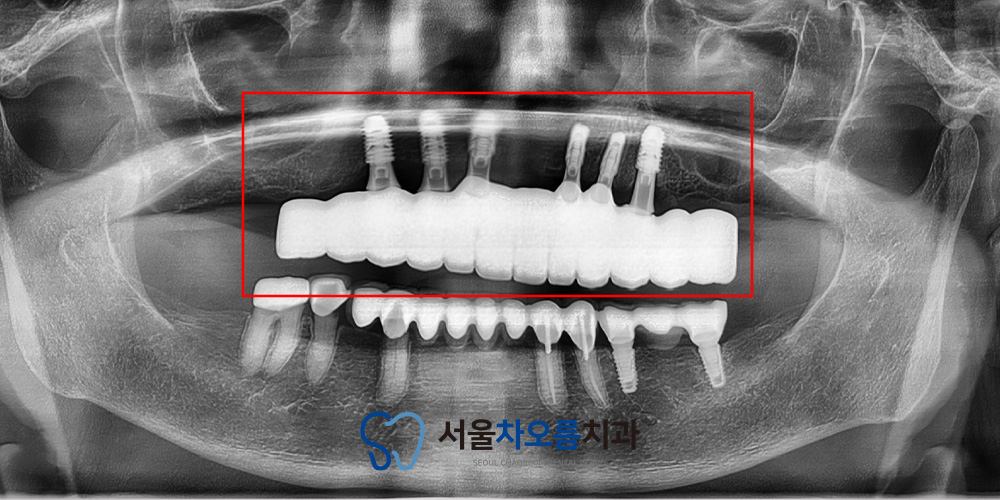

약 4개월간의 치유 기간을 거친 후,

임플란트의 고정 상태와 수치를 확인해보니

특별한 문제 없이 안정적으로

치유가 진행되고 있었습니다.

이에 2차 수술을 진행한 뒤,

맞춤형 지대주와 임시치아를 제작하기 위해

정밀 인상채득을 시행하였습니다.

이후 임시치아 장착 시 아쉬웠던 부분을

보완하여 제작된 최종 보철물을

맞춰보았습니다.

길어보였던 치아가

자연스럽게 조정되면서

전체적인 비율이

한층 균형 있게 다듬어졌습니다.

위쪽의 전체적인 보철물이

들어가기 때문에

교합 또한 세밀하게 조정하여

양쪽으로 균형 잡힌 저작이

가능하도록 맞춰드렸습니다.

이를 통해 씹는 힘이 고르게 분산되면서

턱관절 부담이 줄고,

식사 시에도 훨씬 안정적인

느낌을 받으실 수 있었습니다.